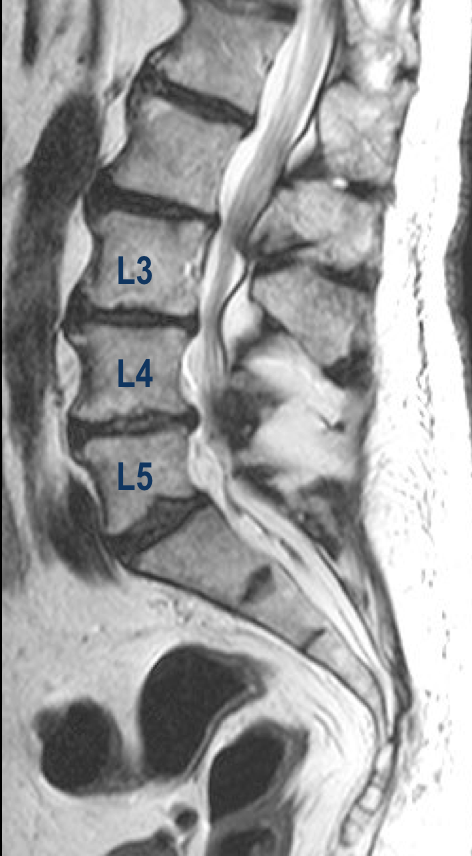

Paciente: JEE

Edad: 83 años

Diagnóstico: Estenosis espinal severa en los segmentos L3-L4, L4-L5

Tipo de Cirugía: Laminotomía más foramininotomía microquirúrgica, mediante Técnica de Y. Hatta, para descompresión del conducto espinal en los segmentos L3-L4 y L5-L5.

Fecha de la cirugía: Abril 19 del 2016